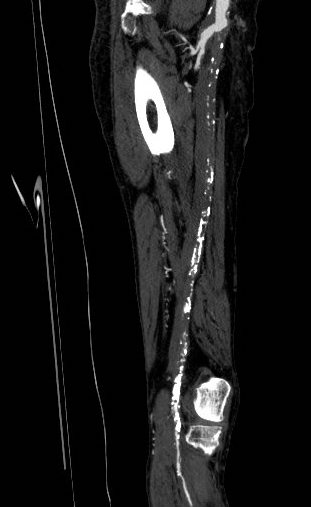

On examination, he had heavy scarring in both groins from prior open incisions healed by secondary intention, a midline laparotomy incision. He had weak bilateral axillary and brachial artery pulses. He had no pulses in either leg. The right foot had gangrene of the distal phalanx of the third toe. The both feet were anemic and painful -the left foot had more dependent rubor. Pulse volume recordings were flat in both legs. TCPO2 was in the 20-40mmHg range at the thighs bilaterally suggesting reduced potential for healing an above knee amputation. Vein mapping showed no suitable saphenous vein in either leg. CTA (figure below) showed both external iliac arteries to be occluded or absent and the common femoral arteries to be occluded or missing bilaterally.

The left femoral bifurcation was preserved and the left SFA was patent into small underfilled tibial vessels. On the right, there was an isolated segment of profunda femoral artery that reconstituted from pelvic collaterals. The right below knee popliteal artery reconstituted and had underfilled but patent three vessel runoff (figure below).

My eye focused on the left iliac graft which perfused the internal iliac artery on that side. The graft was generous, and likely a dilated 8mm graft, and could be exposed via a left lower quadrant retroperitoneal exposure (the transplant exposure). This would allow me to to then tunnel to avoid the terribly scarred groins. On the right side, the obdurator canal could be traversed into the postioer compartment of the thigh -a graft could be sent to the below knee popliteal artery with a side graft to the tiny profunda femoral artery. On the left, the graft could be tunneled laterally near the insertion of the sartorius muscle and onto the superficial femoral artery. All of the incisions would be made in virgin skin, the only redo dissection being digging out the left iliac graft while avoiding injury to the ureter.

The bladder was dissected off the pubis to allow the graft to be tunneled to the right pelvis. A counter incision in the right lower quadrant abdomen and a mid thigh incision mobilizins the anterior compartment muscles to the posterior compartment allowed me to tunnel across the obturator foramen. The obdurator vessels need to be avoided or there will be bleeding. this mid thigh incision allowed exposure of the profunda femoral artery more proximally and allowe the graft to be tunneled anatomically to the below knee popliteal artery for anastomosis. A jump graft was taken off this graft on the thigh to the profunda femoral artery which was small and diseased -no more than 2mm in size. An axillary bypass to this profunda would be doomed to the compromised patency rate published for ax-fem bypasses giving them a bad name. The left superficial femoral artery was exposed and provided outflow to the left iliofemoral bypass which was tunneled far laterally under the inguinal ligament to avoid the scar tissue where the common femoral artery was.